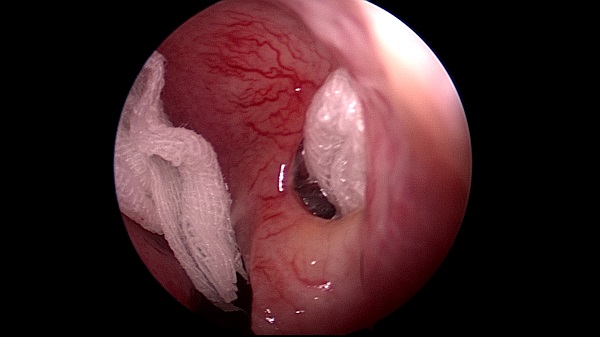

耳鼻咽喉頭頸外科(ke)近日(ri)成(cheng)功爲(wei)一(yi)名(míng)“慢性鼻窦炎伴鼻息肉鼻中(zhong)隔穿孔鼻中(zhong)隔偏曲 ”的(de)中(zhong)年(nian)男性患者,行全麻“鼻內(nei)窺鏡下低溫等(deng)離子(zi)刀(dāo)全組鼻窦開放+窦內(nei)病變清(qing)除術(shù)+雙側鼻息肉切除術(shù)+鼻中(zhong)隔穿孔修補術(shù)+鼻中(zhong)隔偏曲矯正術(shù)+雙側下鼻甲骨折外移術(shù)”。

術(shù)中(zhong)遊離鼻中(zhong)隔穿孔前(qian)、後(hou)、上、下緣黏軟骨膜,取方(fang)形軟骨部(bu)分(fēn)篩骨垂直闆部(bu)分(fēn)犁骨組織修補穿孔松解穿孔周圍黏膜瓣并保留血供,穿孔被完全覆蓋(gai),去除鼻中(zhong)隔左側偏曲的(de)篩骨垂直闆,開放雙側上颌窦、額窦、篩窦、左側蝶窦清(qing)除窦內(nei)病變,去除雙側中(zhong)鼻道息肉。術(shù)程(cheng)順利,無副損傷。術(shù)後(hou)患者恢複良好,病人(ren)目(mu)前(qian)已出院。